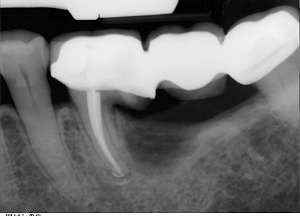

Zaletą amputacji  jest fakt, że zdrowa część zęba pozostaje w kości i po wygojeniu rany pozabiegowej, może służyć jako filar pod koronę lub most protetyczny. Poniższe zdjęcie rentgenowskie pokazuje wykorzystanie amputowanego zęba do utrzymania mostu.